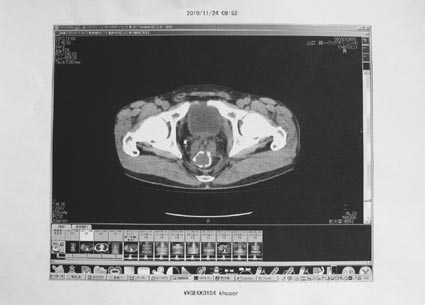

2)CT検査・下部内視鏡

<所見> 異常なし